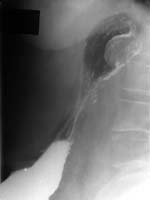

При рентгенологическом исследовании (Рис. 1, 2) — положение, размеры, форма желудка обычные. На фоне газового пузыря в кардиальном отделе желудка, на задней стенке последнего — дополнительная тень округлой формы, однородная по структуре, с четкими ровными контурами, размерами 3х4см. В нижележащих отделах желудка и 12 п. к. патологии не выявлено. Было сделано заключение : "Рак кардиального отдела желудка, экзофитная форма".

Рис. 1. Прямая прекция. На фоне газового пузыря в кардиальном отделе желудка на задней стенке имеется дополнительная тень округлой формы с четкими ровными контурами, размерами 3х4см.

Рис. 2. Боковая проекция.